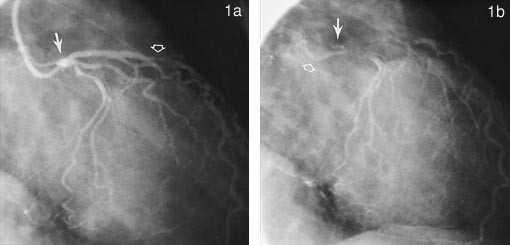

Venstre ventrikkel fungerte normalt. I venstre koronararterie var det en uttalt stenose med svært uregelmessig restlumen ved avgangen fra aorta (fig 1a). I tillegg hadde pasienten trekarsykdom med uttalte sentrale stenoser i alle grener.

Etter fjerning av kateteret fra venstre koronararterie ble det registrert en liten kontrastansamling i veggen i hovedstammen (fig 1b), men arterien tømte seg raskt for kontrast, og pasienten hadde ingen brystsmerter eller EKG-forandringer.